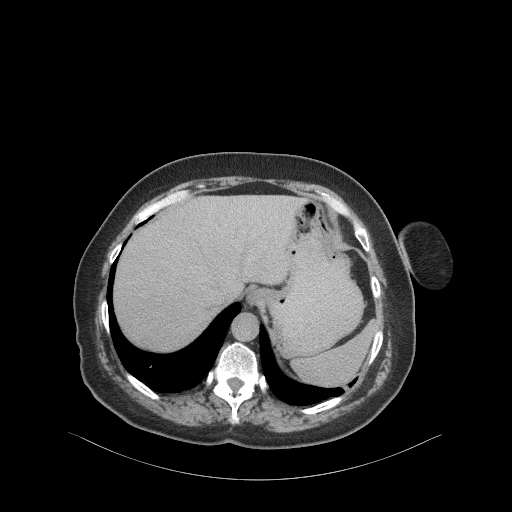

Reconstructed NATIVE CT scan (cycle consistency)

Full window (WL 1023.5, WW 4095 β Low β1024, High +3071)

Actual HU range: [-850.6, 624.8]

Lung window (WL -600, WW 1500 β Low β1350, High +150)

Actual HU range: [-850.6, 150.0]

Mediastinum window (WL 40, WW 400 β Low β160, High +240)

Actual HU range: [-160.0, 240.0]